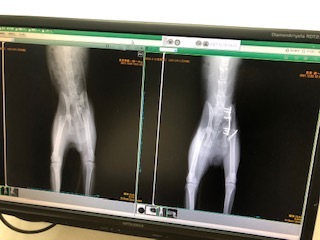

2日間の管理入院の後、無事に骨盤にプレートを入れる手術が成功しました。

※手術翌日の猫ちゃんです。